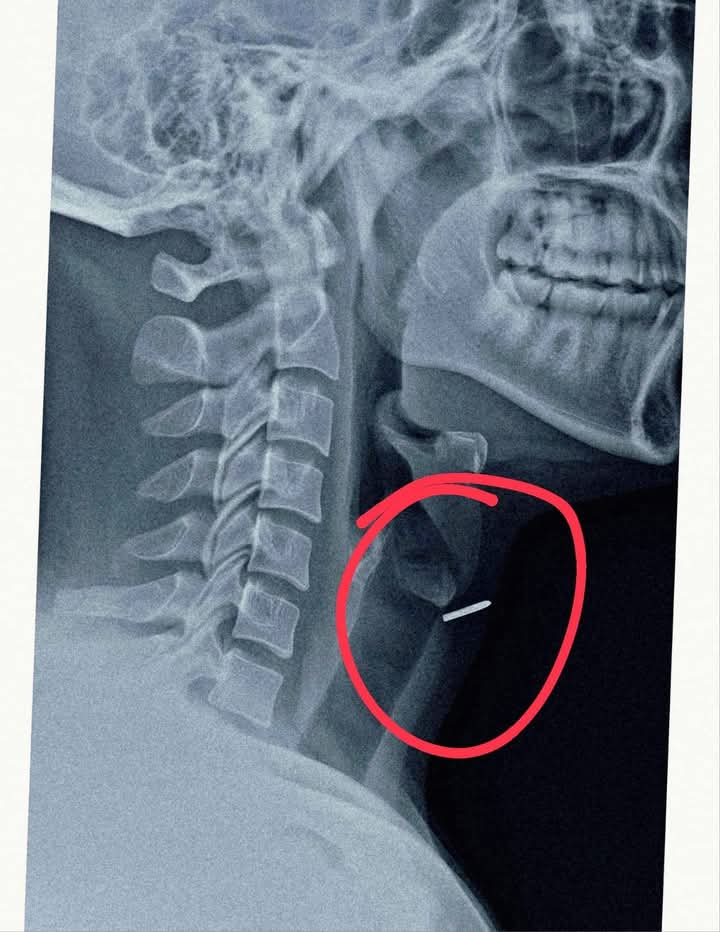

आधुनिक कील लगाने वाली मशीन के खराब होने से हुआ हादसा* लखीमपुर-खीरी। तकनीक जितनी सहायक होती है, कभी-कभार एक चूक से उतनी ही घातक व जानलेवा भी हो जाती है। महेवागंज में एक ऐसा ही मामला सामने आया है जहां फर्नीचर बनाने वाले कारपेंटर के साथ ऐसा ही खतरनाक हादसा हुआ, जब वह एक स्वचालित कील लगाने वाली मशीन से काम कर रहा था। अचानक मशीन में खराबी आ गई और एक कील तेज़ी से उल्टी दिशा में चलकर उसकी गर्दन में घुस गई घायल युवक दीपू (28) को स्वशासी राजकीय चिकित्सा महाविद्यालय संबद्ध जिला अस्पताल मोतीपुर ओयल लाया गया। मरीज पहले से एक्स रे करा कर लाया था, जांच करने में पता चला कि कील सीधी थायरॉइड ग्रंथि में जाकर फंस गई है और श्वास नली के ठीक पास स्थित है। यह स्थिति अत्यंत गंभीर थी क्योंकि थोड़ी सी भी लापरवाही जानलेवा साबित हो सकती थी इस संवेदनशील स्थिति को गंभीरता से लेते हुए सहायक आचार्य ईएनटी सर्जन डॉ. मनोज शर्मा ने लोकल एनेस्थीसिया में ऑपरेशन किया और कील को सफलतापूर्वक सर्जरी कर बाहर निकाला। ऑपरेशन के बाद मरीज की स्थिति पूरी तरह सामान्य रही और उसे उसी दिन अस्पताल से छुट्टी दे दी गई। साथ ही किसी तरह की समस्या होने पर तत्काल दिखाने के लिए एडवाइस किया गया है डॉ. शर्मा ने बताया कि यह मामला दुर्लभ और चुनौतीपूर्ण था। “कील श्वसन नली के बेहद नज़दीक थी। हमें अत्यधिक सावधानी बरतनी पड़ी ताकि कील निकालते समय कहीं श्वास नली में ना चली जाए” प्रधानाचार्य डॉ वाणी गुप्ता ने बताया कि इस घटना ने यह साबित कर दिया कि तकनीक का इस्तेमाल करते समय पूरी सावधानी बरतनी चाहिए, जहाँ तक हो सके स्वचालित मशीनों को इस्तेमाल करते समय सुरक्षा उपकरण जरूर पहनें। किसी भी प्रकार की दुर्घटना होने पर तत्काल नजदीकी स्वास्थ्य केंद्र पर पहुंचे। सीएमएस डॉ आरके कोली ने बताया कि किसी भी दुर्घटना के बाद किसी की जान बचाने के लिए “समय” सबसे महत्वपूर्ण कारक है, समय रहते मरीज को अस्पताल पहुंचने से चिकित्सकों को स्थित अति गंभीर नहीं होती है और अधिकतर मामलों मे मरीज की जान बचायी जा सकती है। जिला अस्पताल एवं हमारा स्टाफ हर समय किसी भी प्रकार की दुर्घटनाओं ने निपटने के लिए तैयार रहता है।